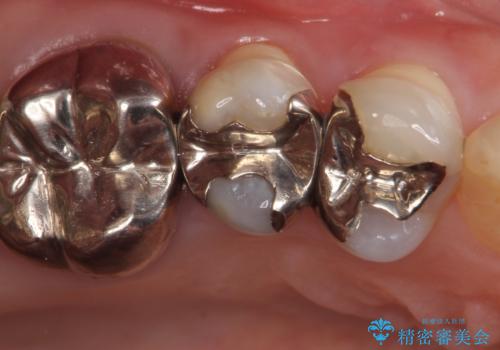

- 右上5番目の歯がなにもしなくてもズキズキ痛むので診て欲しいといらっしゃった方の症例です。

診査の結果神経を保存するのは困難だったため、根管治療を行った後、オールセラミッククラウンによる補綴を行いました。